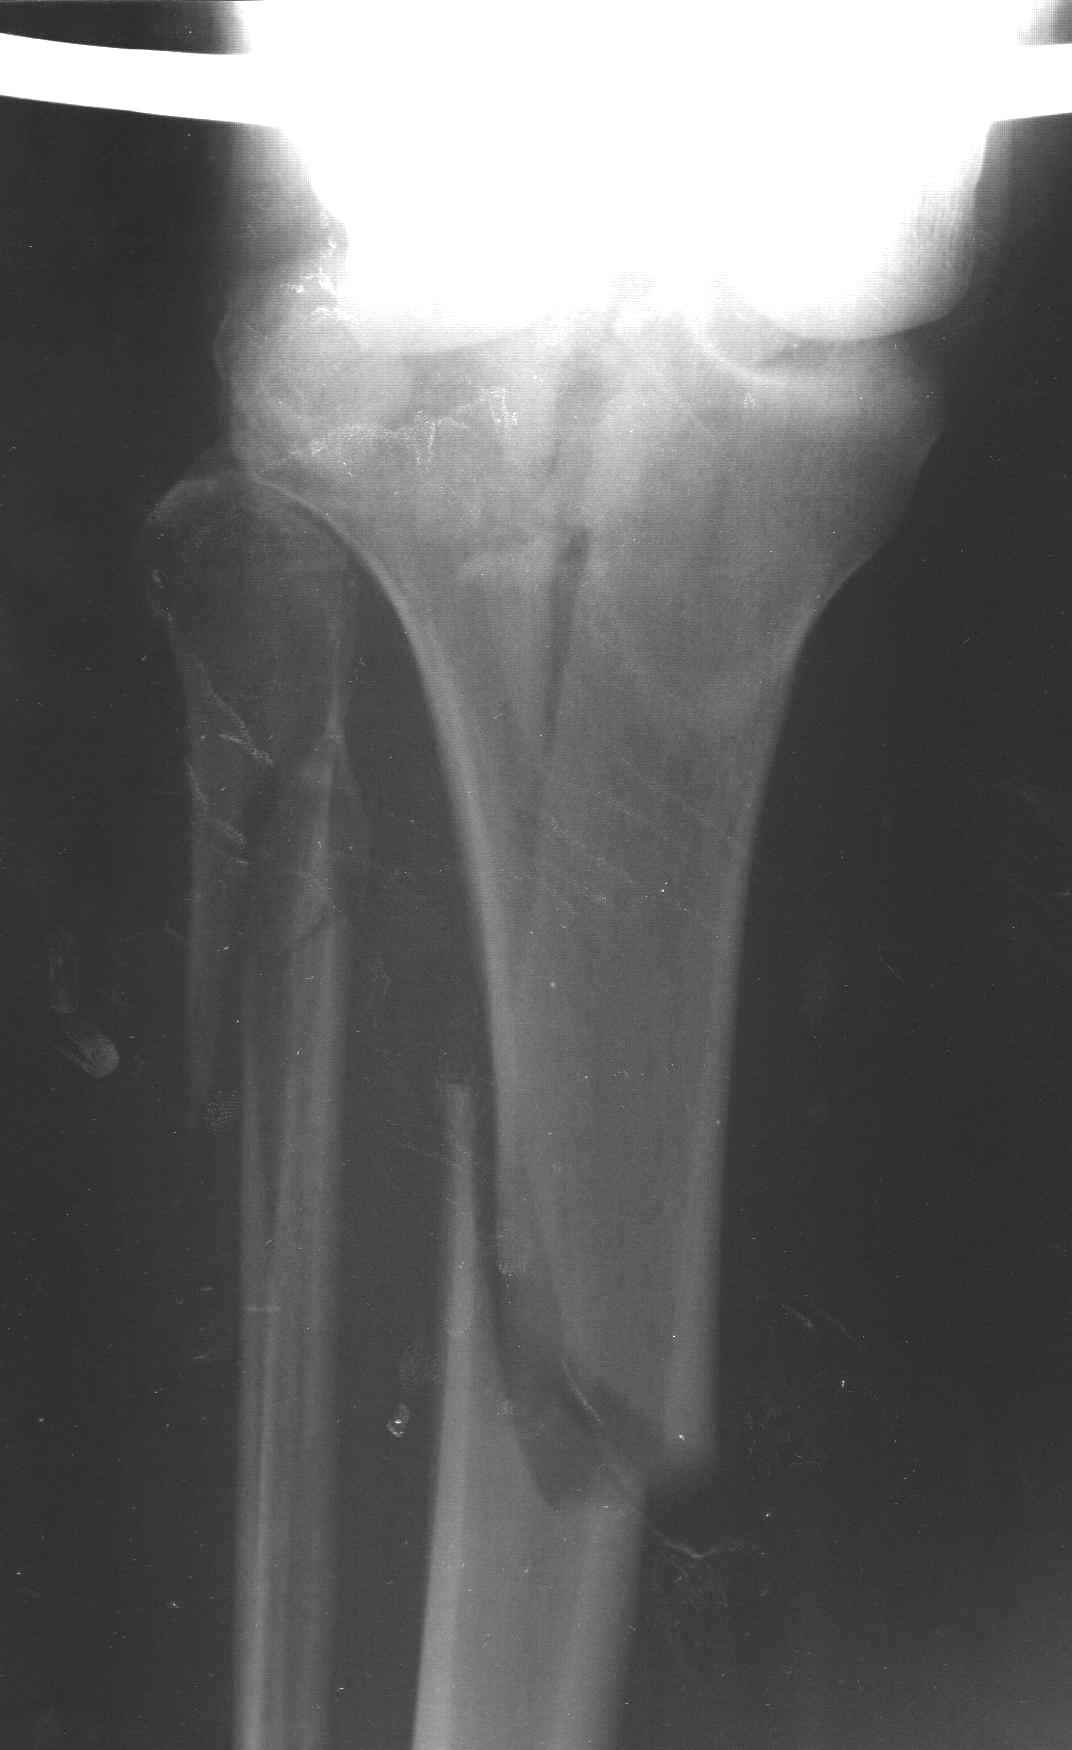

Пациенту сделали КТ - ухитрились сделать на шине Белера (не давал положить прямую ногу) - срезали передний отдел. Планируется на пятницу (24.12) на операцию - синтез длинной мыщелковой LCP-пластиной Synthes :). Отек ближе к слову умеренный (окружность голени +4 см по сравнению со здоровой). КТ и снимок на вытяжении прилагаются.

Трудно поверить, что разрекламированная Ортопедическая школа Восточной Украины позволяет такие странные снимки? На прямом снимке сохранен общий контур плато, но не известна судьба импрессии суставной поверхности. На полубоковой?, оставлен без репозиции задне-медиальный отдел, и навряд ли после такой фиксации можно удовлетвориться результатом.

Здесь как раз тот случай, когда результат зависит не только от мастерства хирурга, но и от наличия современных методов исследования. Например, КТ которая поможет рассчитать направления шурупов и установку импланта. Кроме этого, поможет определиться с доступом.

На представленных предоперационных срезах КТ огромный задне-медиальный фрагмент расположен больше кзади, чем медиально. Для планирования, кроме поперечных срезов, надо ориентироваться на корональные срезы, которые укажут топографию верхушки медиального фрагмента.

Представленные снимки не информативны, нужны отдельные качественные снимки коленного сустава и голени без ротации.